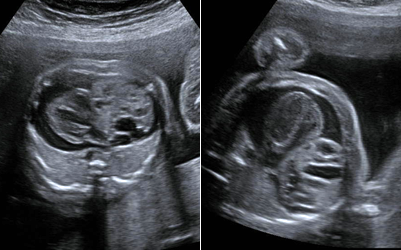

Myelomeningocele high resolution ultrasound.

Dandy Walker Malformation.